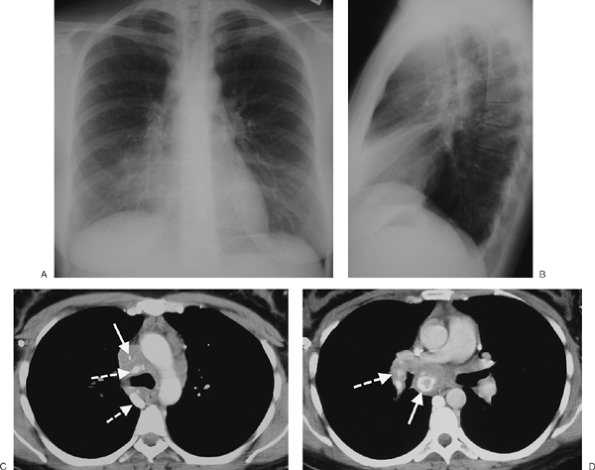

FIGURE 6-16. Benign teratoma. A: PA chest radiograph shows abnormal opacity in the right hemithorax, some of which is caused by pleural effusion, and mediastinal shift to the left. B: Lateral view shows abnormal opacity in the retrosternal area. C: CT scan shows an anterior mediastinal mass of homogeneous soft tissue attenuation (M), compressing a narrowed superior vena cava (solid arrow) and right pulmonary artery (dashed arrow), and right pleural effusion (E).

Calcification, ossification, teeth, or fat may be visible on a chest radiograph and on CT scans. CT scans may show cystic components and/or a fat–fluid level. A cyst wall with curvilinear calcification is often present. Unequivocal fat within the mass confirms the diagnosis of teratoma, but the absence of fat or calcium does not exclude a teratoma (Fig. 6-16).

Imaging features of malignant germ cell tumors are similar to those of benign teratoma except that fat density is not noted and calcification is rare. The malignant tumors grow rapidly, and metastases may be seen in the lungs, bones, or pleura. The adjacent mediastinal fat planes may be obliterated. The tumors may be of homogeneous attenuation or show areas of contrast enhancement interspersed with rounded areas of decreased attenuation from necrosis and hemorrhage. Rarely, coarse tumor calcification may be seen (9).